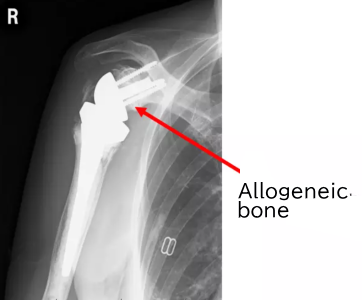

Postoperative X-ray

- We will show you the course over six years after surgery.

X-ray at six months after surgery

X-ray six years after surgery